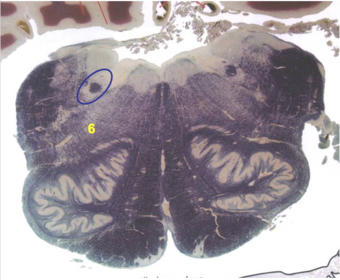

| Superior cerebellar peduncle | |

| Dentate nucleus | |

| Fastigial nucleus | |

| Anterior spinocerebellar tract | |

| Spinal nucleus of V | |

| Spinal tract of V | |

| Middle cerebellar peduncle | |

| Superior vestibular nucleus | |

| Medial lemniscus | |

| Trapezoid body | |

| Ventral trigeminothalamic tract | |

| Superior olive | |

| Longitudinal pontine fibers (corticospinal tract) | |

| Transverse pontine fibers (dark fibers) | |

| Pontine nuclei (pale) | |

| Central tegmental tract | |

| ALS | |

| Medial longitudinal fasciculus | |